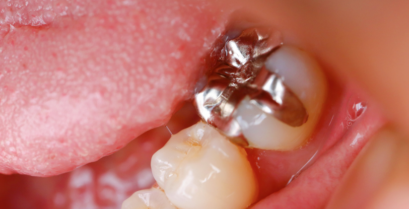

金属の詰め物や被せ物、いわゆる「銀歯」といった歯科金属を使用しない治療で、コストパフォーマンスとクオリティーオブライフ(QOL)を向上させます。